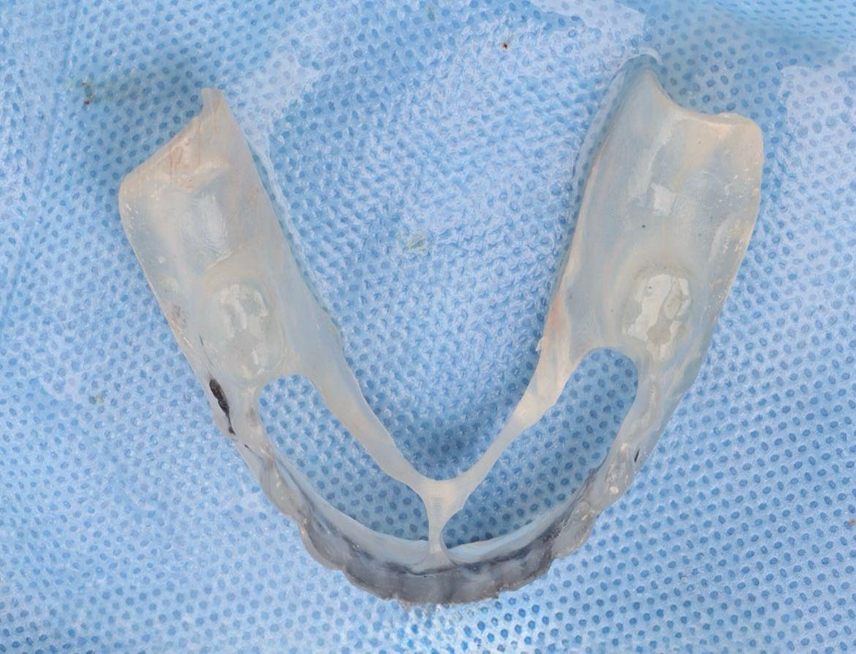

Paciente de 62 anos, do sexo feminino, sem comorbidades e história médica pregressa, apresentava severa reabsorção óssea em regiões anteriores e posteriores da mandíbula devido a uma peri-implantite (Figuras 1A e 1B). Feita a remoção dos implantes, a paciente optou por utilizar uma prótese total mucossuportada até a nova intervenção com prótese do tipo protocolo inferior. Após seis meses, a mandíbula encontrava-se cicatrizada (Figura 2). Como parte do protocolo diagnóstico, foi realizada tomografia computadorizada pela técnica do duplo DICOM. Com a severa perda óssea em região anterior de mandíbula, optamos por realizar a cirurgia de forma guiada, aumentando a previsibilidade e precisão da cirurgia. Os arquivos obtidos foram exportados para o software CoDiagnostiX, possibilitando a realização do planejamento reverso e o subsequente posicionamento virtual dos implantes (Figura 3). Com base no planejamento, optou-se pela instalação de quatro implantes Implacil Osstem CM AR Due Cone (3,5 x 7 mm), associados a mini-cônicos de 1,5 mm (Figuras 4A, 4B, 4C, 4D e 4E). A partir da tomografia da prótese da própria paciente, confeccionaram-se duas guias cirúrgicas: uma guia de pino de fixação (Figura 5) e uma guia de fresagem para a instalação dos implantes (Figura 6). Durante o procedimento cirúrgico, inicialmente foi posicionada a guia de pino de fixação para fresagem dos pinos de fixação e orientação da sequência cirúrgica (Figura 7). Após essa etapa, a guia foi substituída pela guia de fresagem dos implantes (Figura 8), utilizada para a fresagem e inserção dos implantes planejados (Figura 9). Concluída a instalação, optou-se por seguir o fluxo analógico, com a adaptação dos mini-cônicos 1.5 mm (Figura 10), realização da transferência de moldagem com silicona de adição leve e sutura com fio absorvível Vycril 6-0. O guia inicial foi adaptado com broca Maxicut, possibilitando sua utilização como molde de orientação para o laboratório protético (Figura 11). Após a moldagem, foram posicionadas as tampas de proteção sobre os implantes. Na fase protética, transcorridas 48 horas do procedimento cirúrgico, foi realizada a prova clínica da barra metálica e dos dentes (Figura 12). Na etapa subsequente, 72 horas após a cirurgia, procedeu-se à instalação e entrega do protocolo mandibular inferior e radiografia prévia, reabilitando funcional e esteticamente a paciente em curto espaço de tempo (Figuras 13A e 13B).